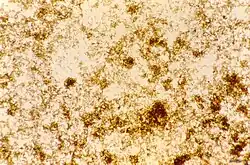

The malaria parasite, therefore, detoxifies the hematin, which it does by biocrystallization—converting it into insoluble and chemically inert β-hematin crystals (called hemozoin).[13][14][15] In Plasmodium the food vacuole fills with hemozoin crystals, which are about 100–200 nanometres long and each contain about 80,000 heme molecules.[4] Detoxification through biocrystallization is distinct from the detoxification process in mammals, where an enzyme called heme oxygenase instead breaks excess heme into biliverdin, iron, and carbon monoxide.[16]

Hemozoin crystals have a distinct triclinic structure and are weakly magnetic. The difference between diamagnetic low-spin oxyhemoglobin and paramagnetic hemozoin can be used for isolation.[33][34] They also exhibit optical dichroism, meaning they absorb light more strongly along their length than across their width, enabling the automated detection of malaria.[35] Hemozoin is produced in a form that, under the action of an applied magnetic field, gives rise to an induced optical dichroism characteristic of the hemozoin concentration; and precise measurement of this induced dichroism (Magnetic circular dichroism) may be used to determine the level of malarial infection.[36]